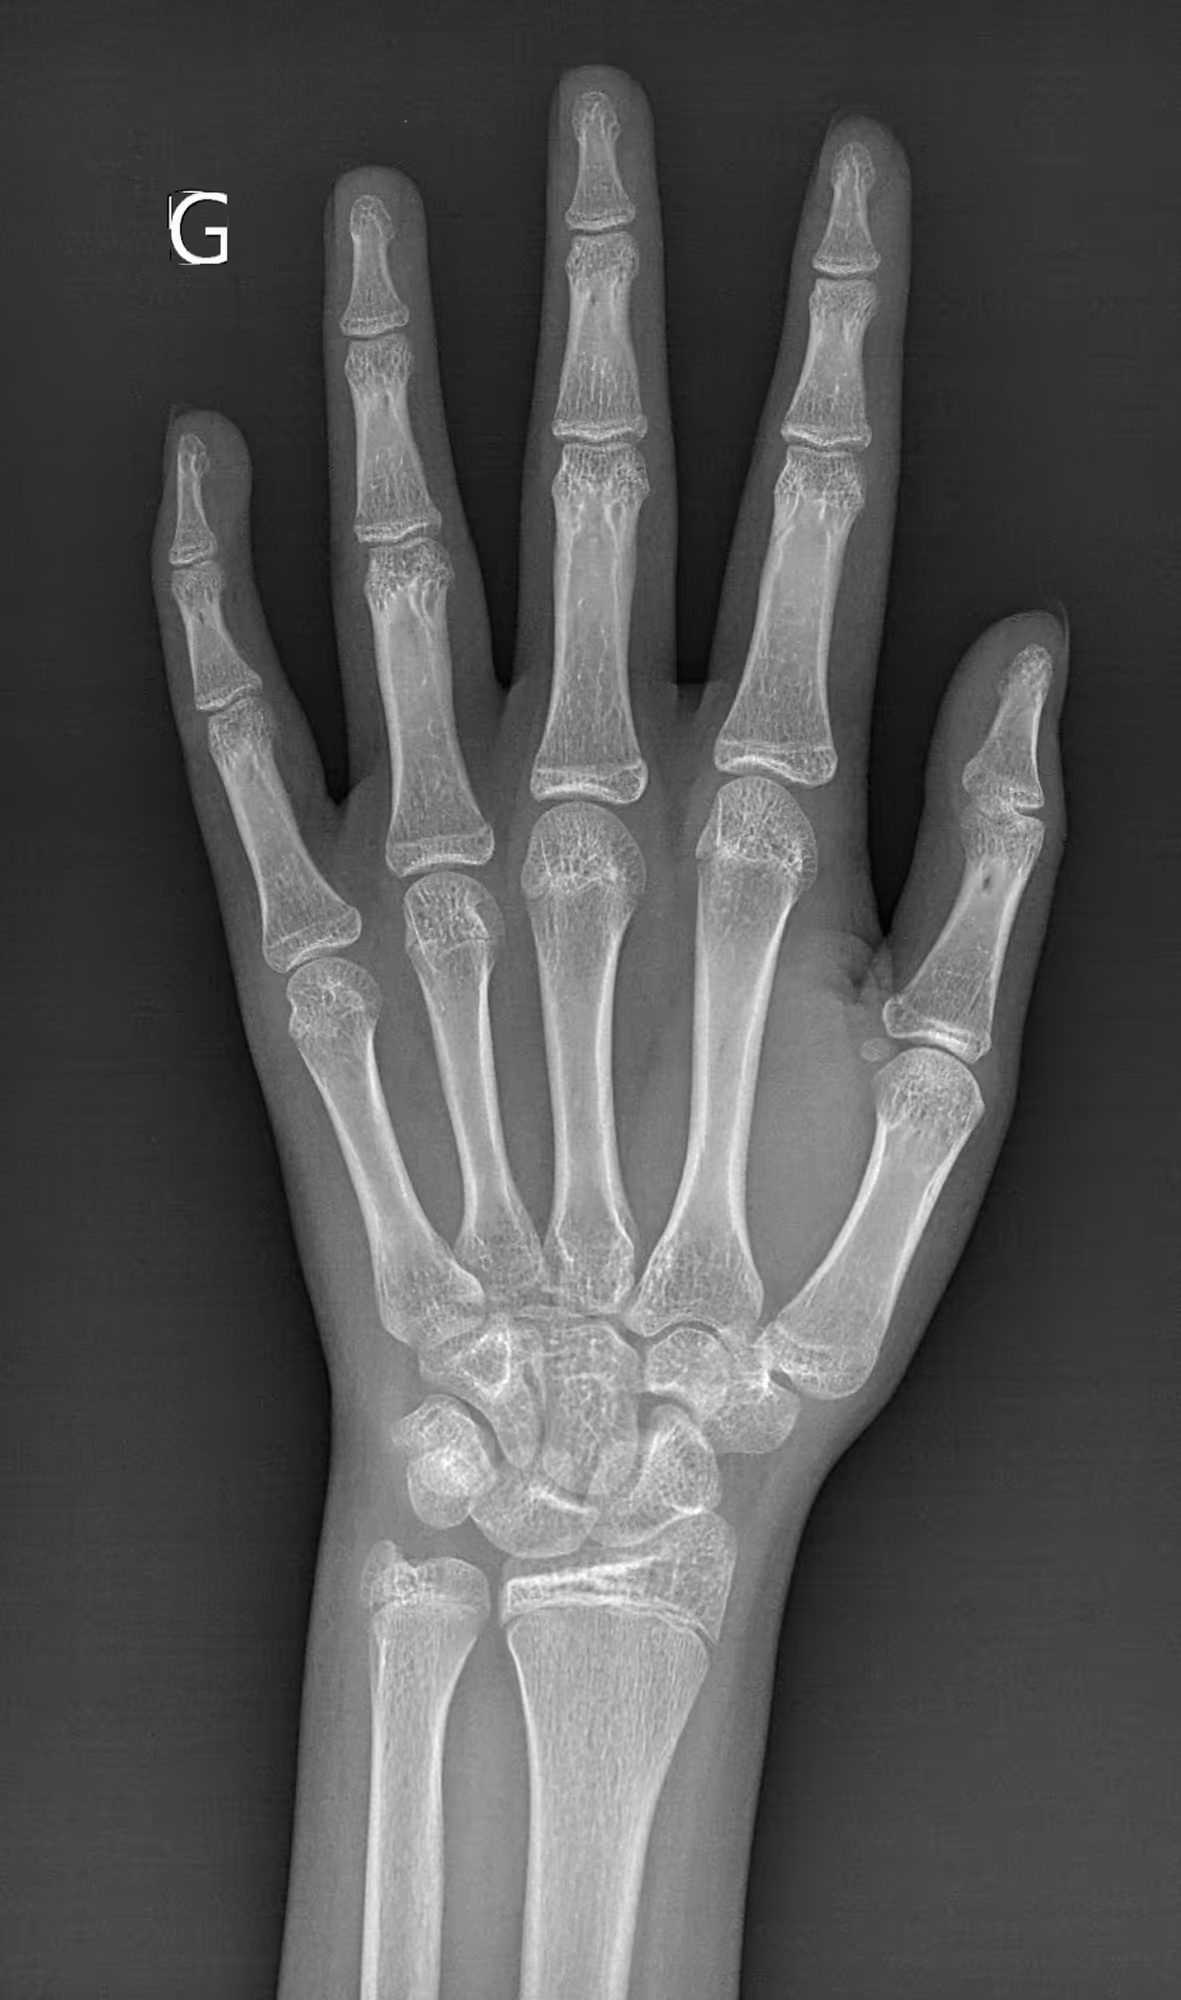

An 11-year-old girl presenting for bone age assessment due to signs of early puberty.

BoneAge analysis indicates an advanced bone age compared to the patient’s chronological age.

BoneAge is designed for frontal hand acquisition using the Greulich & Pyle method.